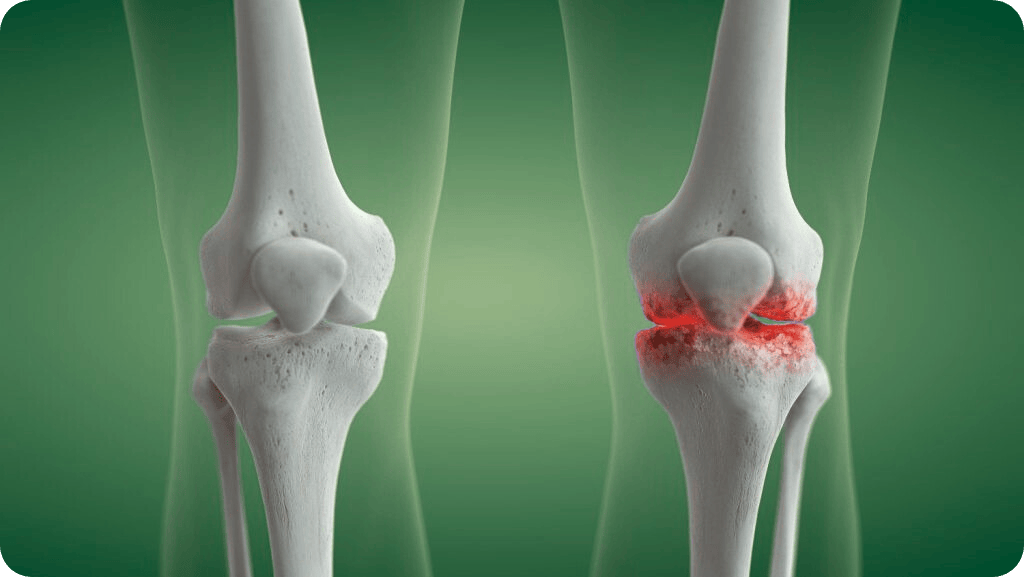

What is Knee Arthritis?

Knee arthritis is a leading cause of knee pain for adults over 40. The most common type, osteoarthritis, occurs when the smooth cartilage within the knee wears away and bones begin rubbing together causing pain, swelling, and stiffness. Other types include rheumatoid arthritis and post-injury arthritis, both of which may impact your knee health.